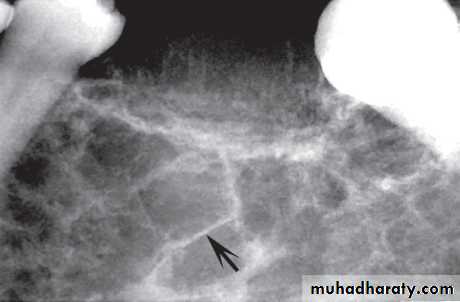

Nasopalatine duct/incisive canal cyst

This cyst develops from epithelial remnants of the nasopalatine duct or incisive canal.

• Site: Midline, anterior maxilla just posterior to the upper central incisors.

• Shape: — Round or oval (superimposition of the nasal septum or anterior nasal spine may cause the cyst to appear heart-shaped or resemble an inverted tear drop)

— Monolocular.

• Outline: — Smooth

—Well defined

—Well corticated (unless infected).

• Radiodensity: Uniformly radiolucent